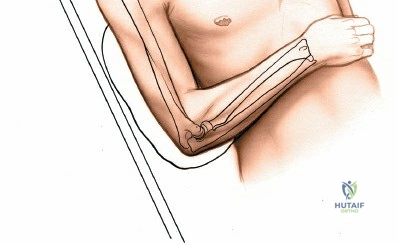

Place the patient supine on the operating table. The affected upper extremity is extended onto a radiolucent hand table or arm board. The shoulder should be abducted to approximately 90 degrees, and the elbow extended. A pneumatic tourniquet is applied high on the brachium. The setup must allow for unimpeded use of intraoperative fluoroscopy (C-arm), which should be positioned parallel to the arm board to allow for easy anterior-posterior and lateral imaging without compromising the sterile field.

Accurate identification of surface landmarks is the first step in a successful Henry approach. Palpate the biceps tendon, a stout, taut structure crossing the anterior elbow joint just medial to the brachioradialis muscle. Next, palpate the brachioradialis itself, the fleshy muscle forming the lateral border of the cubital fossa. Finally, identify the styloid process of the radius distally. Note that when the forearm is fully supinated (the anatomic position), the radial styloid is truly lateral.

Make a straight or gently curved incision beginning at the anterior flexor crease of the elbow, just lateral to the biceps tendon. Extend this incision distally toward the styloid process of the radius. The exact length and placement of the incision are dictated by the specific pathology; the approach is highly modular, and often only the proximal, middle, or distal third of the incision is required.